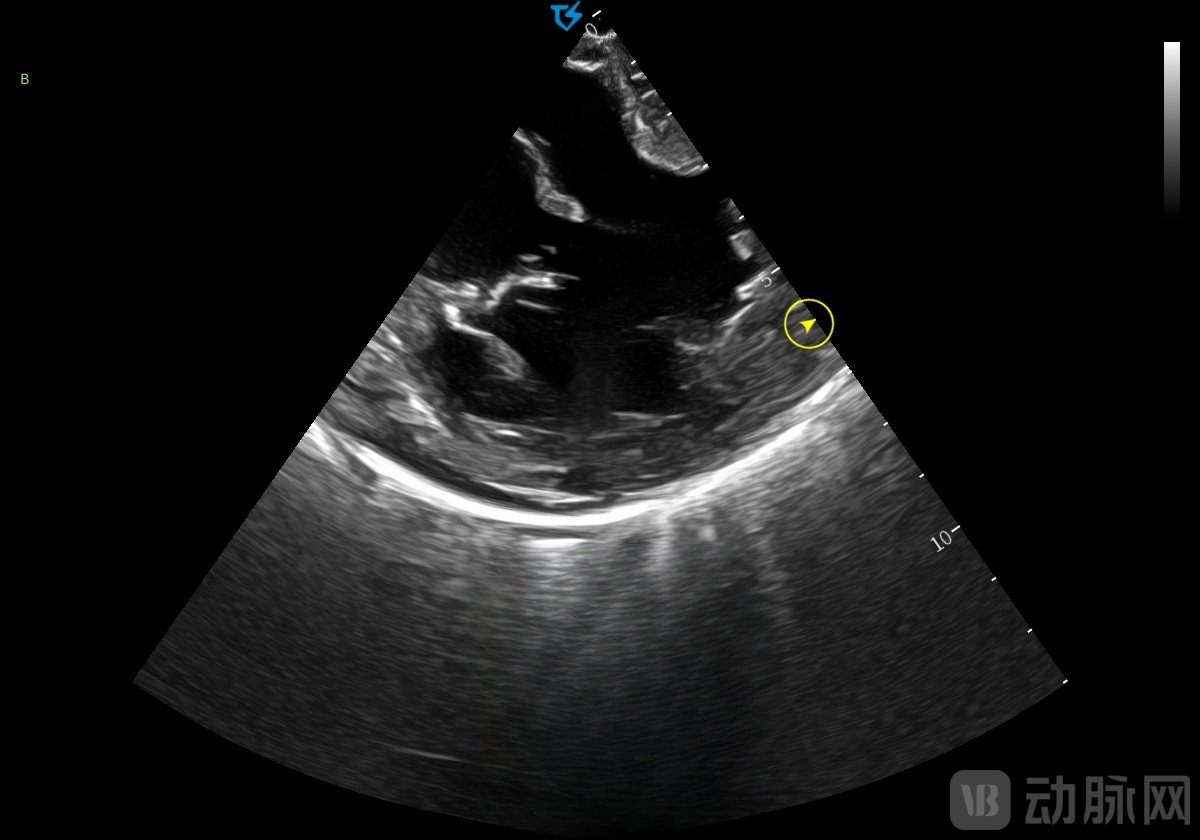

术中穿刺后,术者操作TINGSN 4D ICE导管经股静脉入路,进入右心后观察各腔室结构及瓣膜情况。在4D ICE引导下完成房间隔穿刺,并观察术前心包。建立通路后,首先行肺静脉隔离术,然后在实时动态三维超声影像监测下观察左心耳,引导封堵器械进入并完成封堵。完成干预后,撤出输送系统,并通过二维及三维图像确认心包完整。术后患者体征平稳,转入病房。相较传统X线透视,ICE技术使辐射暴露时间缩短62%,手术总耗时减少约30分钟。

"重构的心腔内立体实时影像与心腔内二维超声影像精度匹配,同步实现360°全景观察。"孔祥清教授特别指出,"这种多维信息整合能力对降低并发症发生率和提高手术消融效率具有重要价值。"临床团队反馈,该设备在瓣膜反流评估、心耳分叶测量等关键环节的成像质量,已达到国际主流产品水平。